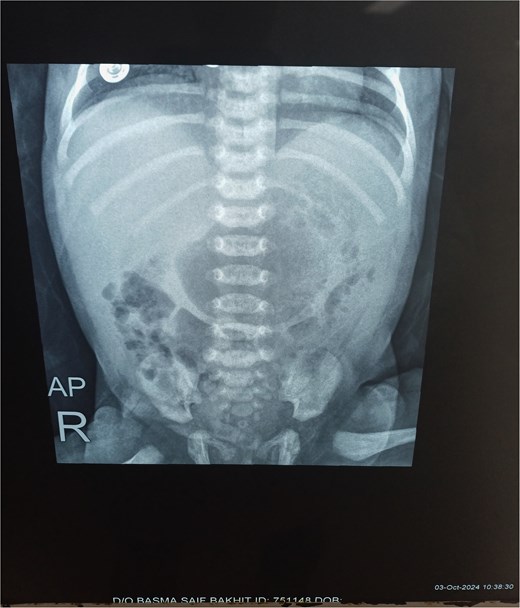

Chest X-ray was normal (Fig. 1). A water-soluble contrast meal was performed (Fig. 2) and the contrast arrested at the gastric antrum for 45 min. Then there was normal opacification of the duodenum and jejunum on follow-up films after 1.15 and 1.3 h. A complementary ultrasound (US) was done along with the contrast study and it showed a thick mucosal fold (4 mm) at the gastric antrum situated 1 cm away and on the left side of the duodenum. The pyloric canal was open and patent and had a normal wall thickness (1.5 mm) excluding hypertrophic pyloric stenosis.

The patient had a naso-jejunal tube for feeding, instead of performing a feeding jejunostomy, and an orogastric tube for gastric decompression. The patient was left on nothing per oral until peristalsis was resumed. No drainage tubes were put for fear of infection. Vital signs were checked in the follow-up and an X-ray for chest and abdomen was done after 5 days (Fig. 4) then at 1 week post-operatively to exclude the formation of air under diaphragm. The post-operative period was uneventful, and the patient was discharged after 15 days from admission.